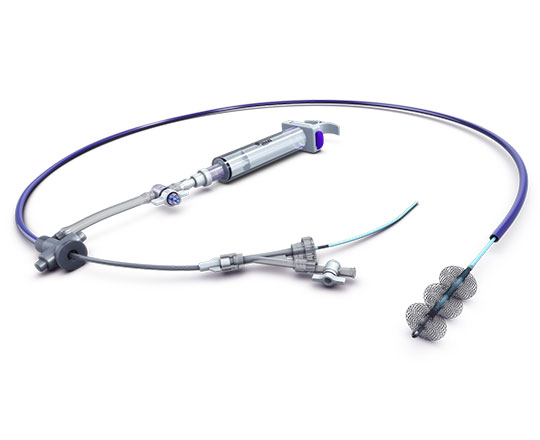

El dispositivo Conformal (Conformal Medical, Estados Unidos) está diseñado para adaptarse a la anatomía de la orejuela de cada paciente y disminuir la necesidad de ecografías transesofágicas y anestesia general durante el implante.

Tiene un esqueleto de nitinol con dos filas de 20 anclajes que se fijan a la pared de la orejuela, con un recubrimiento matricial de espuma en forma de tapón. En la parte superior de este, la expuesta al contacto sanguíneo, lleva un recubrimiento con tejido de politetrafluoroetileno expandido (ePTFE) que evita la trombosis del dispositivo1.

La matriz de espuma permite sellar con mayor eficacia posibles fugas de otros dispositivos, y se adapta a la mayor parte de anatomías de la orejuela con solo dos tamaños. La gran ventaja del recubrimiento de ePTFE es que reduce de manera importante la formación de trombos sobre el dispositivo, sobre todo cuando la anticoagulación o la antiagregación están contraindicadas.